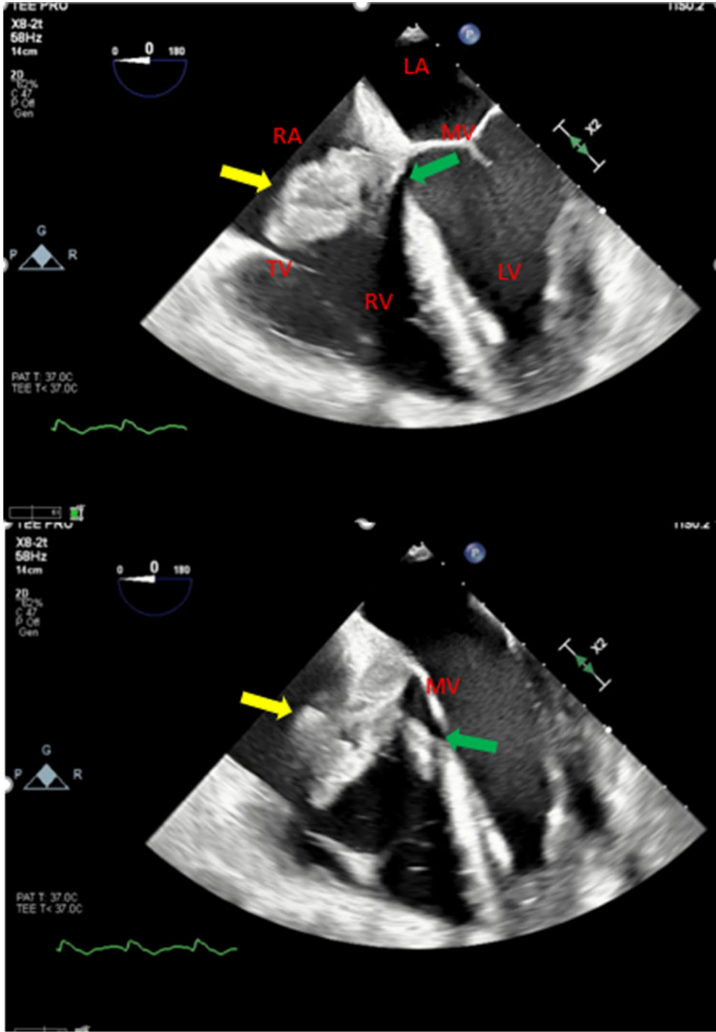

紧急TEE检查证实了室间隔完全侵蚀和生物主动脉瓣膜开裂,二维图像清晰显示右心房内大型赘生物和相关的Gerbode缺损。多普勒超声进一步显示主动脉根部感染沿瓣周扩展,室间隔膜部侵蚀入右心房,左心室流出道与右心房之间存在连续性左向右分流,并伴有重度主动脉反流。